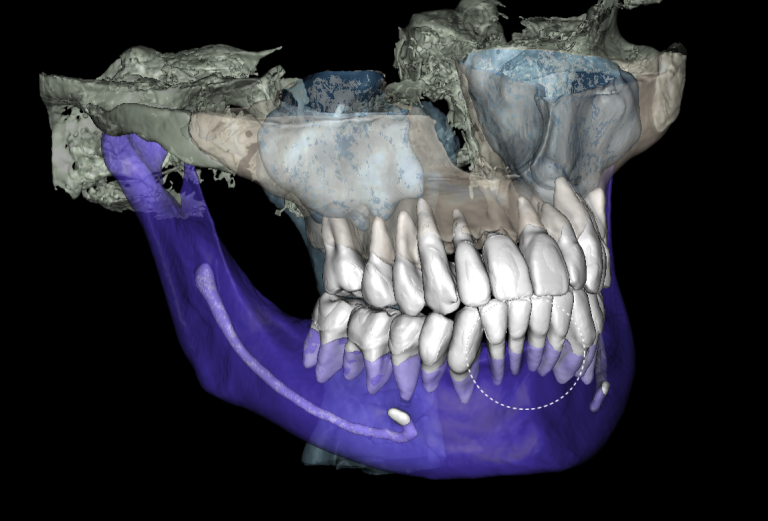

Combining DICOM data and intraoral scans in Diagnocat STL module allows for the creation of 3D models

Based on these data, stereolithographic models were created and a surgical template for gingivectomy was planned